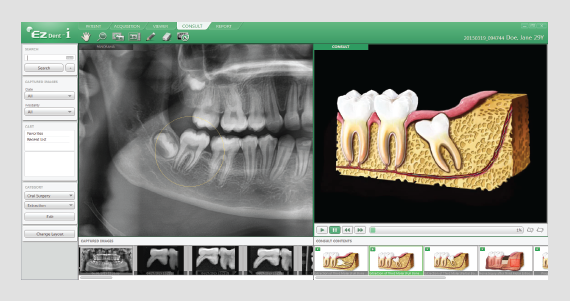

DIAGNÓSTICO BASADO EN 3D

Función de recorte permite ver el volumen de calidad y secciones de la misma en cualquier dirección.